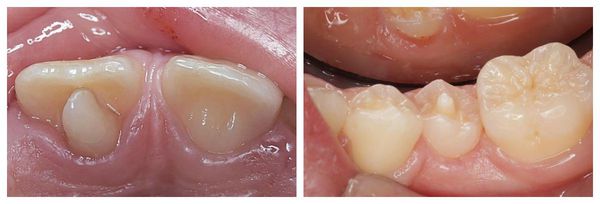

Odbudowa zęba stożkowatego

Leczenie mikrodoncji (mikrodoncja, zbyt małe zęby) polega na połączeniu terapii ortodontycznej z kompleksową rehabilitacją protetyczną, której celem jest poprawa estetyki uśmiechu i przywrócenie prawidłowej funkcji zgryzu.

Etap ortodontyczny obejmuje:

• przemieszczanie zębów (przesuwanie zębów) w celu ich wyrównania i korekcji ustawienia;

• zamykanie przerw między zębami (diastemy, tremy), które często towarzyszą mikrodoncji;

• stworzenie miejsca w łuku zębowym pod przyszłe odbudowy protetyczne.

Po zakończeniu leczenia ortodontycznego następuje etap rekonstrukcji estetycznej, który może obejmować:

• odbudowę zębów materiałem kompozytowym,

• pokrycie zębów licówkami (licówki, veneers),

• założenie koron protetycznych (korony) – gdy konieczna jest pełna korekta kształtu i wysokości zęba.

Dzięki temu zęby uzyskują prawidłowe proporcje, naturalny kształt i kolor, a pacjent odzyskuje estetyczny uśmiech oraz prawidłową funkcję żucia.